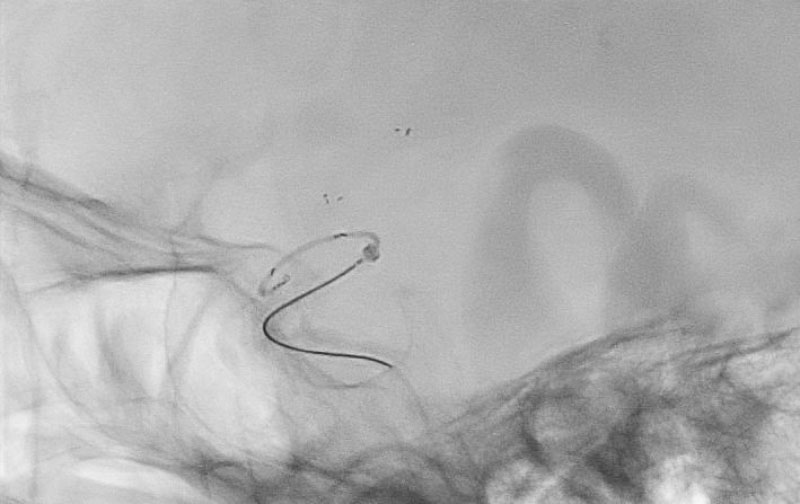

症例 '22年2月

No.

1186

'22年2月5日

脳外主幹動脈血栓症脳梗塞

80代

救急外来

手術写真

治療

前

中

後